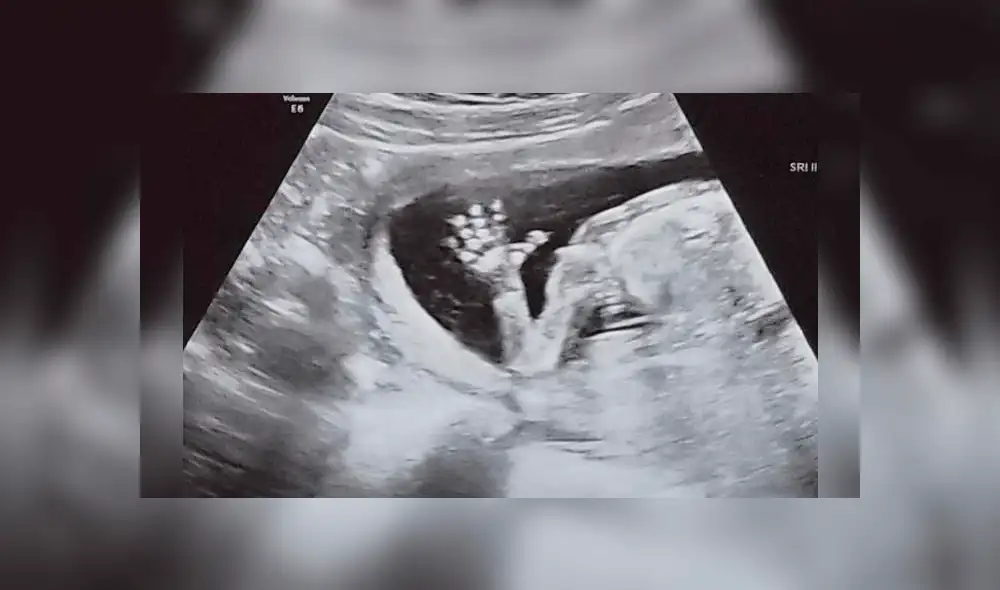

Era octubre de 2017 cuando Bethany McMillin descubrió que tenía útero didelfo, una rara malformación donde hay dos úteros, dos vaginas y dos cuellos uterinos. Para aquel entonces, ella tenía diez semanas de embarazo.

McMillin tuvo su señal de esperanza cuando la ecografía de las nueve semanas reveló que su bebé tenía latidos sanos. La pequeña Maeve nació en septiembre de 2019 y hoy tiene cinco meses de edad.